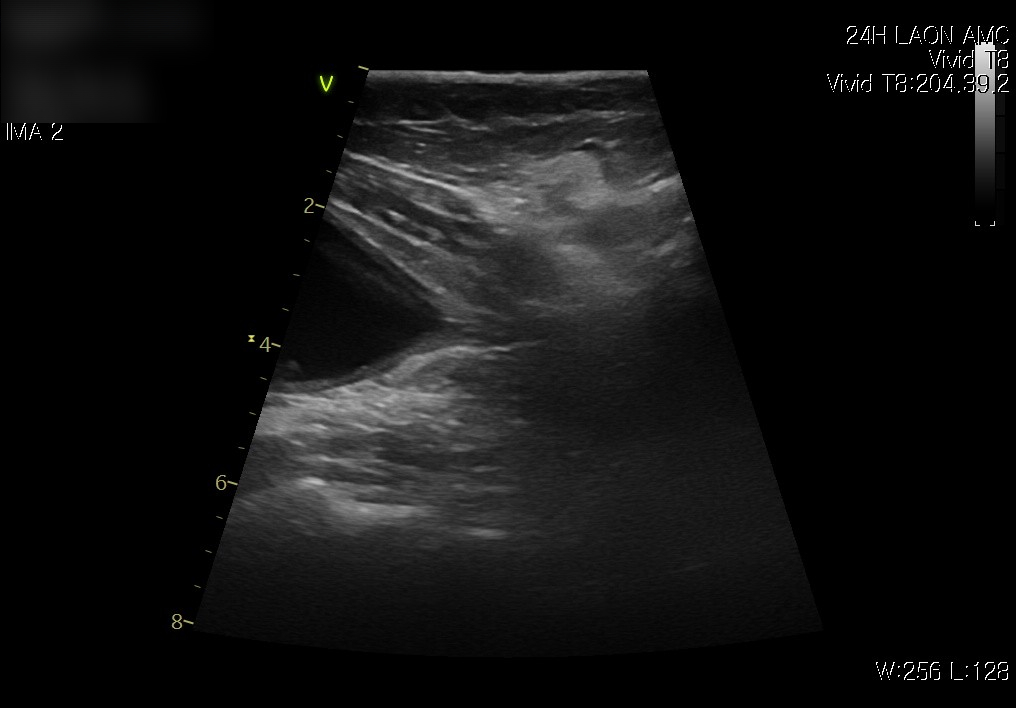

다음은 복부 초음파 검사 결과입니다.

내원 시 방광 요도 사진 / 출처: 라온동물메디컬센터

방광 초음파에서는 방광 내 염증성 변화와 소변 잔류가 관찰되었습니다.